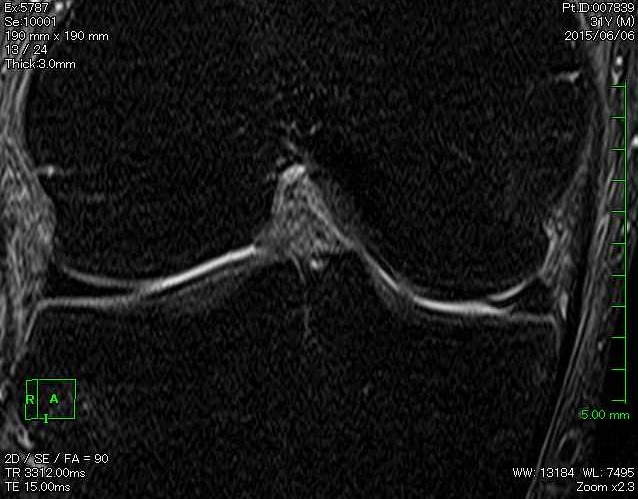

後になって撮影したMRI画像を見返してみると、 この時点ですでに半月板にも大きなダメージが入っていたことが分かります。

正面に近い断面の画像で、健側はきれいな三日月型を保っているのに対し、

損傷側は半月板が途切れ、裂けた部分がめくれ上がっているような形に見えました。

医師ではないので「ここが絶対こうだ」と断定はできませんが、

このめくれた部分が、のちに起こるロッキング(膝が引っかかって動かなくなる現象)の原因になっていたのだろうと感じています。